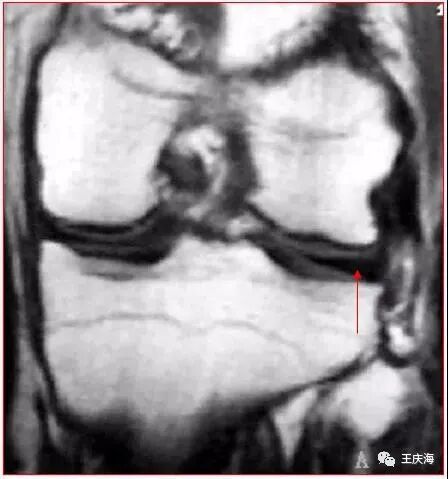

冠状面(图A)见外侧半月板体部宽度增宽,横断面(图B)示外侧半月板环较小。

大盘状半月板覆盖75%以上的一侧胫骨平台

矢状面T2WI(上图)显示半月板覆盖整个一侧胫骨平台,形态不规则,信号不均匀。